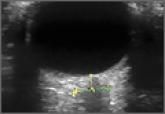

Does Optic Nerve Sheath Diameter Ultrasonography Permit Accurate Detection of Real-Time Changes in ICP?

- Christopher K. Schott, MD, MS, RDMS